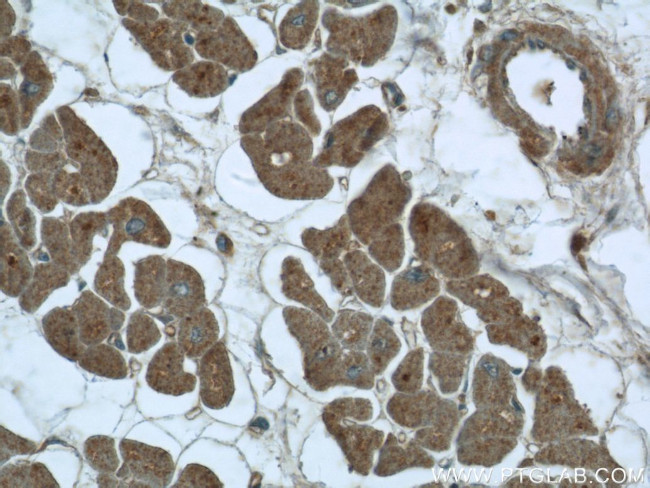

DDX58 Antibody in Immunohistochemistry (Paraffin) (IHC (P))

DDX58 Antibody (25068-1-AP) in IHC (P)

Immunohistochemistry of paraffin-embedded human heart tissue slide using 25068-1-AP ( DDX58 Antibody) at dilution of 1:50 (under 40x lens). {{ $ctrl.currentElement.advancedVerification.fullName }} 验证信息 View more